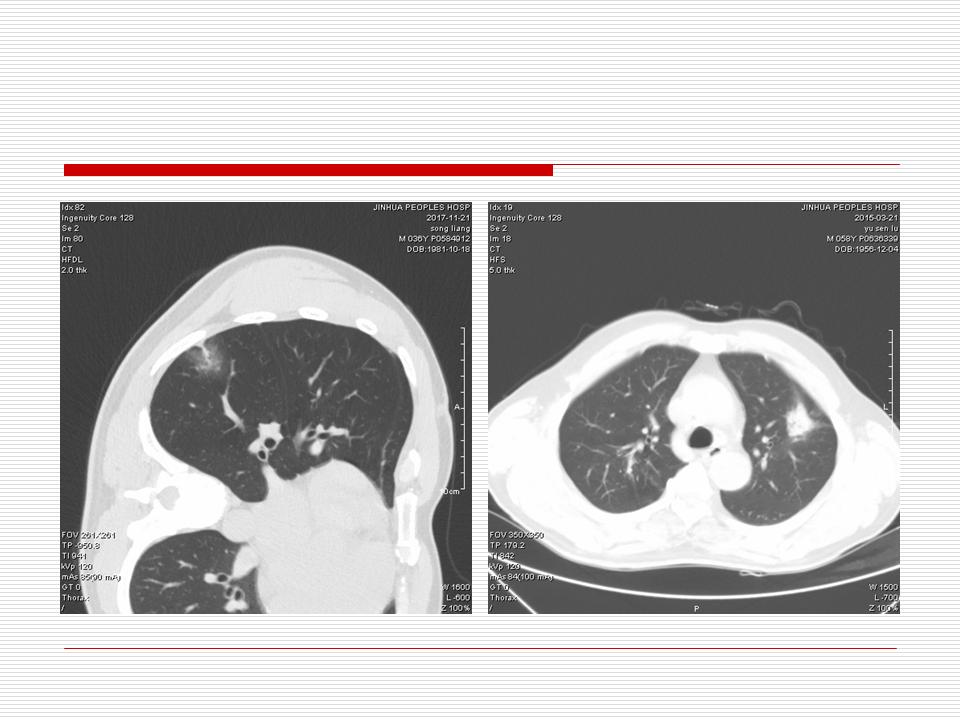

肺部阴影永恒且最重需要鉴别的是:到底是炎症还是肿瘤?但临床的病例中的影像表现难以界定或有些肿瘤特征,同时又有些炎症特点是非常常见的情况。作为临床医生我们怎么去总结分析,并找到之所以是炎症或之所以是肿瘤的细微差别或特点非常重要,也非常有用。2019.12.7浙江省2019年胸心外科学学术年会在宁波召开时,我的临床病例分析与经验总结<那些像肺癌的炎症与像炎症的肺癌>获得在大会交流的机会,以下为该PPT的内容,与你分享,希望对同道有益,有借鉴与启迪。若有探讨与进一不完善的建议,欢迎文末留言讨论: